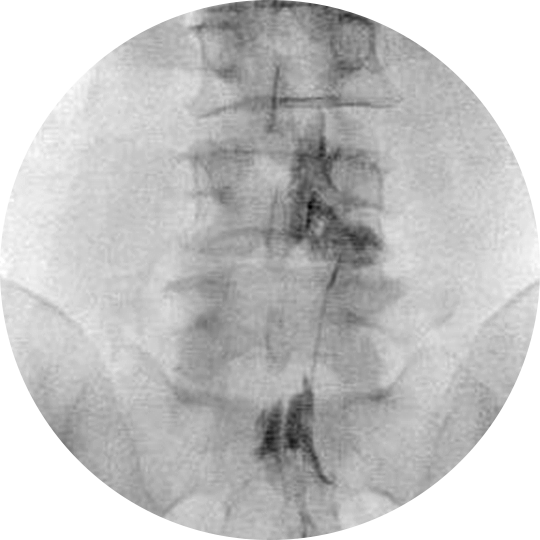

C-arm 영상장치를 보면서 신경손상의 위험성을 줄인 스프링장치가 내장된 도관을 통증의 원인이 되는 부위에 위치시킵니다.

그 후 염증을 완화시키는 약물, 척수와 척추관의 유착을 분리하는 히알우로니다제 분해 효소 또는 고장성 식염수 등을 경막외강에 주입시켜 염증을 없애고 유착을 제거합니다.